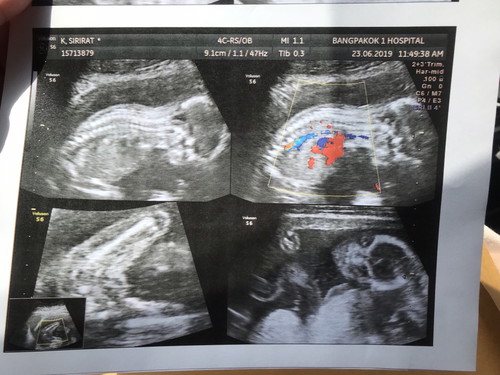

18w ท้องแรก กำหนดคลอด 24/11/62ลุงหมอบอกลูกสาวค่ะ

แต่คุณพ่อผิดหวังเล็กน้อย อยากได้ลูกชาย แม่น้ำหนักไม่ขึ้นเลย แต่ลูกน้ำหนักตามเกณฑ์ปกติดี